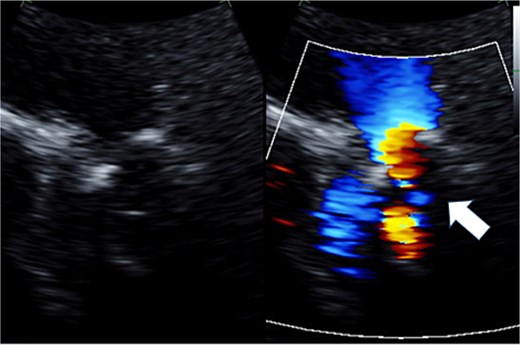

Cardiopulmonary bypass was established with ascending aorta and bicaval cannulation. The right atrium was incised, the previous TV ring was removed, and a tissue valve (MITRIS 27 mm; Edwards Lifesciences Corporation, Irvine, CA, USA) was implanted. The pulmonary artery was opened to the RVOT, and the previously implanted valve was removed (Fig. 3). The valve leaflet was not calcified but was thickened and shortened, showing a restricted opening. PVR was performed again with a 29 mm INSPIRIS valve. RVOT was closed using Gore-Tex artificial vessels graft (expanded polytetrafluoroethylene; W. L. Gore & Associates, Flagstaff, AZ, USA) for patching.

Intraoperative view: the pulmonary artery and right ventricular outflow tract opened with the previously implanted pulmonary valve explanted.